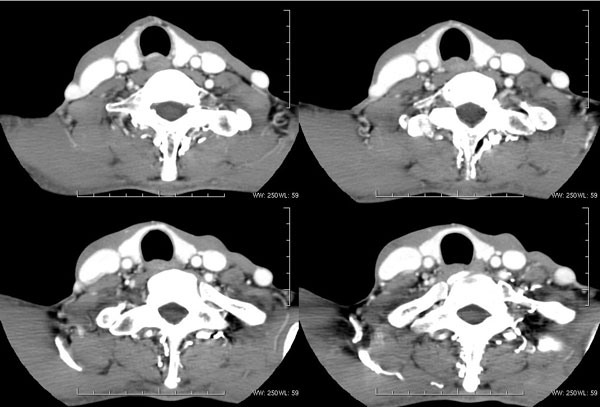

| 男性,57岁。反复声嘶1年,加重半年。 体检:喉粘膜充血,会厌肿胀,上举差,喉室及双声带窥视欠清。              蚂蚁发言:考虑喉癌(声门型)?双侧颈鞘周围淋巴结转移? 徐飞发言:有无呛水?根据病史要考虑球麻痹,脑干应检查 弯三角发言:考虑喉结核,应检查其它部位有无结核 卜一发言:喉腔右侧壁弥漫性软组织增厚,喉腔变窄。支持:喉癌(声门型)!另:双侧颈部多枚淋巴结肿大! 结果: 支纤镜检查:会厌板肿胀,右会厌咽侧壁肿胀,右杓状小结见结节样肿物,喉室肿胀,双声带肿胀、充血,左声带见菜花样肿物,触及易出血,取活检。 病理诊断:高分化鳞状细胞癌。 免疫组化:ck(h)(+++)、pcna(++)、p53(++)、ck(l)(-)。 原贴地址:http://www.radinet.com.cn/forum_view.asp?forum_id=4&view_id=34703 |